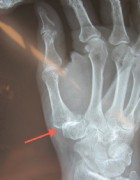

Finger-end joint stiffening and middle joint replacement in rheumatoid patients.

Left: Red Arrow: Horn-like deposits as an sign of osteoarthritis, yellow arrow: complete destruction of the joints, with inflammation and pain at rest and at work.